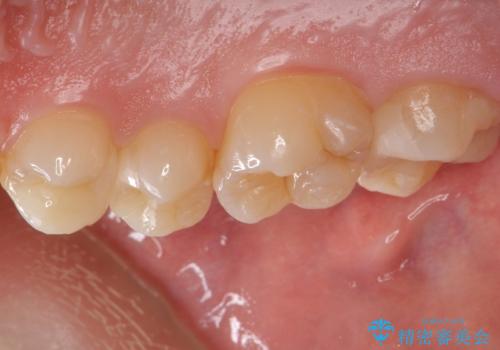

歯と歯の間の虫歯 セラミックインレーでの治療

虫歯の除去後セラミックインレーでの修復処置をしていきます。

- 右上457 セラミックインレー 77,000円×3本費用は治療当時の料金となります

歯と歯の間は虫歯の好発部位とされています。

適合の良いインレーでの修復をすることで再発を防止します。